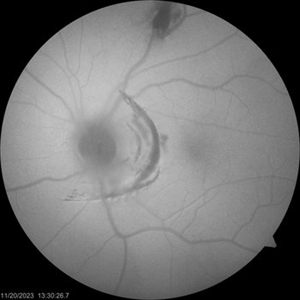

Choroidal Rupture Autofluorescence

Nov 26 2023 by stephen oconnell

Autofluorescence better defines extent of choroidal rupture after blunt trauma - closed fist

Condition/keywords: Choroidal Rupture